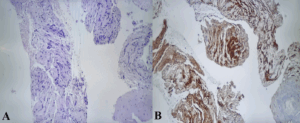

Histological examination (Figure 3) revealed a spindle-cell proliferation with peripheral lymphoid cuffing, while immunohistochemistry demonstrated sAddonstrong S-100 positivity and negativity for actin, desmin, cytokeratins, chromogranin, CD117, and DOG1.

Figure 3. Histopathological and immunohistochemical findings. Spindle-cell proliferation with peripheral lymphoid cuffing (H&E) – A, and diffuse positivity for S-100 – B.